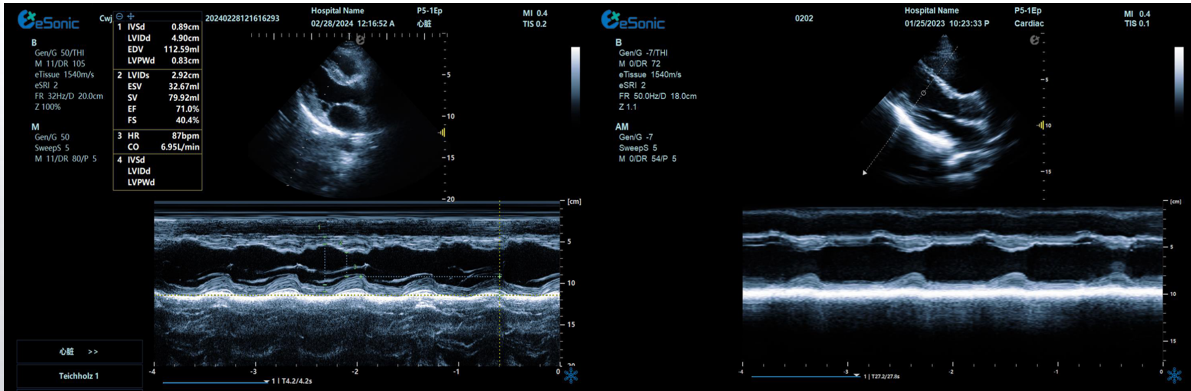

相关心脏应用功能--M型、解剖M型

M型-最常用的心功能检测法;高血压病除二维观察外,其室壁增厚及心腔大小的改变,均也可通过M型测量而获得

解剖M型-适用于心尖上翘者、瘦长体形者、室壁瘤形成等...

相关心脏应用功能--M型、解剖M型技术总结:

M型超声是评估心脏功能的重要方法之一,通过其高速的取样帧频,可以将心脏各个阶段的运动状态显示出来。

M型超声是评估心脏功能的重要方法之一,通过其高速的取样帧频,可以将心脏各个阶段的运动状态显示出来。